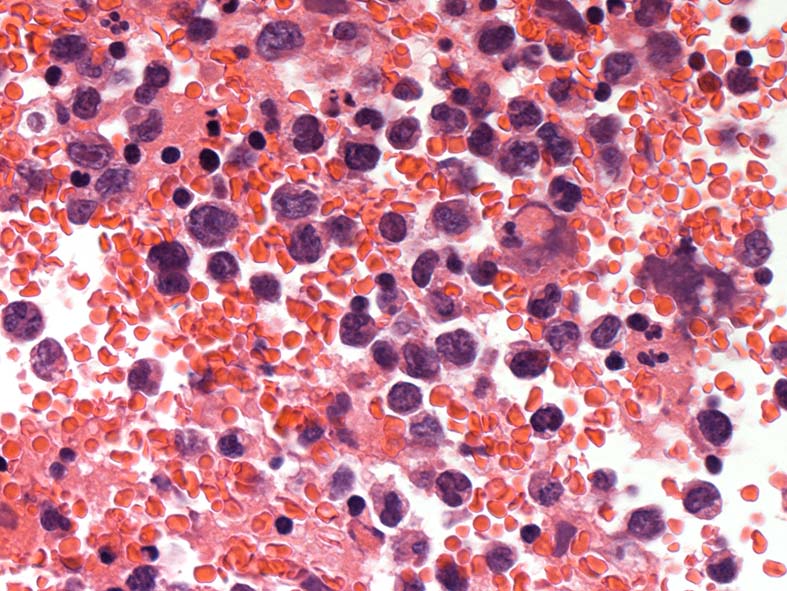

心タンポナーデの診断で心嚢液穿刺ドレナージ. 心嚢液内に多数の異型細胞増加が認められた.心嚢液smear標本. Giemsa染色

小型リンパ球の3-4倍, 空胞の多い青色調の細胞質をもった大型異型細胞が増殖. 核クロマチンは微細顆粒状, 繊細で核小体が1-数個認められる. 二核の異型細胞がある.

ALL-L3やBurkittリンパ腫細胞に類似した腫瘍細胞で, 疾患説明のplasmablastsやALKの細胞とは形態が異なって見える.

胸水セルブロック: effusion lymphomaの場合, IHCなどの精査はcell brockで行うことになる.

心嚢水セルブロックHE染色: 小リンパ球の3倍から5倍ほどの大型異型細胞が多数増加している. 核は類円形, くびれをもつ多型核が見られ, クロマチンは微細な傾向. 核小体を1-数個もつ.

N/C比は大. 好酸性の細胞質が認められる. セルブロックでは細胞質空胞はあまりめだたない. high-grade lymphoma疑い.